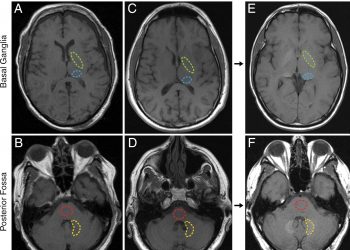

Ибудиласт замедляет атрофию головного мозга, вызванную прогрессирующим рассеянным склерозом

Пациенты с прогрессирующим рассеянным склерозом - с первичным или вторичным течением заболевания - получавшие высокие дозы перорального ибудиласта в клиническом...